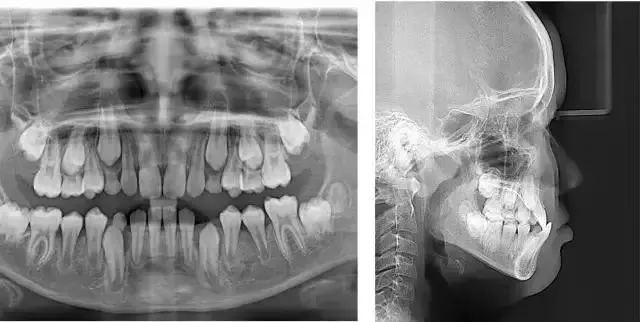

小嘉是一名小学生,随着年龄的增长,小嘉妈妈发现小嘉有地包天倾向,说话也不太清晰,总会被邻居小孩笑话,不敢大笑。

经检查,发现小嘉牙齿下前牙在前,上前牙在后,为“地包天”。经过治疗配合生长改良,使面部比例协调,面部容貌得到改观,再也不怕露出牙齿大笑了。